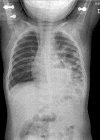

Figure 1

A 15 month old boy presented with restlessness. Bowel sounds were heard on auscultation in the left hemithorax. Chest x ray examination confirmed the diagnosis of DH.